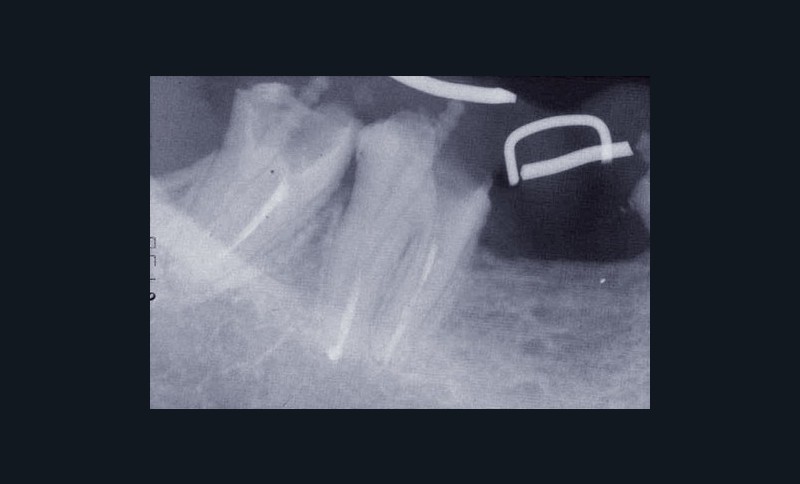

Une patiente âgée de 45 ans consulte à la fin des années 1990 avec une contention en échelle au maxillaire afin de soulager les mobilités des dents antérieures.

Les examens cliniques et radiographiques montrent une parodontite chronique généralisée (fig. 1a à m).

La patiente, en bonne santé, ne fume pas.

Nous décidons d’entreprendre une thérapeutique initiale parodontale classique dans tous les secteurs, y compris l’extraction de 24, un bridge de 45 à 48 avec 46 en pontique, un bridge complet de contention de 17 à 27 sur 11 piliers dentaires et une greffe épithélio-conjonctive sur 31. Cette dernière ne sera jamais réalisée. Le bridge maxillaire permettra de réduire le surplomb antérieur et d’améliorer le sourire de la patiente, ce qui constitue l’une de ses demandes.